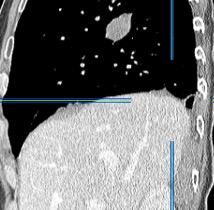

Signos radiológicos TC

Hallifax RJ et al. State-of-the-art: Radiological investigation of pleural disease Respiratory Medicine 2017

Nivel hidroaéreo o burbujas

Forma lenticular o elíptica Ángulos obtusos

> Grasa Extrapleural (60-80%)

Situación no gravitacional (no siempre)

Compresión de estructuras pulmonares

Límite muy bien definido Tabicación

Engrosamiento de la pleura parietal 36/ 59 exudados (61%) 56% de D. paraneumónicos 100% de empiemas Especificidad.. 96%.

Exudado versus trasudado.

Aquino SL, et al. Pleural exudates and transudates: diagnosis with contrast-enhanced CT. Radiology 1994

Signo de la Pleura separada “Split pleural sign”

Capas pleurales de grosor uniforme realzadas por el contraste

No específico de empiema. Indica “exudado”. 68% de pacientes con empiema pleural.

Capas pleurales de grosor uniforme

Realce grasa extrapleural (30%)

> Grasa Extrapleural. (60-80%)

Kraus GJ. Split pleural sign. Radiology 2007